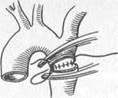

| Рис. 18.6. Операции при коарктации аорты. Объяснение в тексте. |

При коарктации аорты существует четыре типа оперативных вмешательств.

1. Резекция суженного участка аорты с последующим наложением ана

стомоза конец в конец; это выполнимо в том случае, если после резекции

измененного участка без натяжения удается сблизить концы аорты

(рис. 18.6, а).

2. Резекция коарктации с последующим протезированием — показана

при большой длине суженного сегмента аорты или аневризматическом ее

расширении (рис. 18.6, б).

3. Истмопластика. При прямой истмопластике место сужения рассекают

продольно и сшивают в поперечном направлении с целью создания доста

точного просвета аорты. При непрямой истмопластике в аортотомическое

отверстие вшивают заплату из синтетической ткани.

4. Шунтирование с использованием синтетического протеза является

операцией выбора при значительной длине суженного участка коарктации, кальцинозе или резком атеросклеротическом изменении стенки аорты. Шунтирование применяется сравнительно редко (рис. 18.6, в).